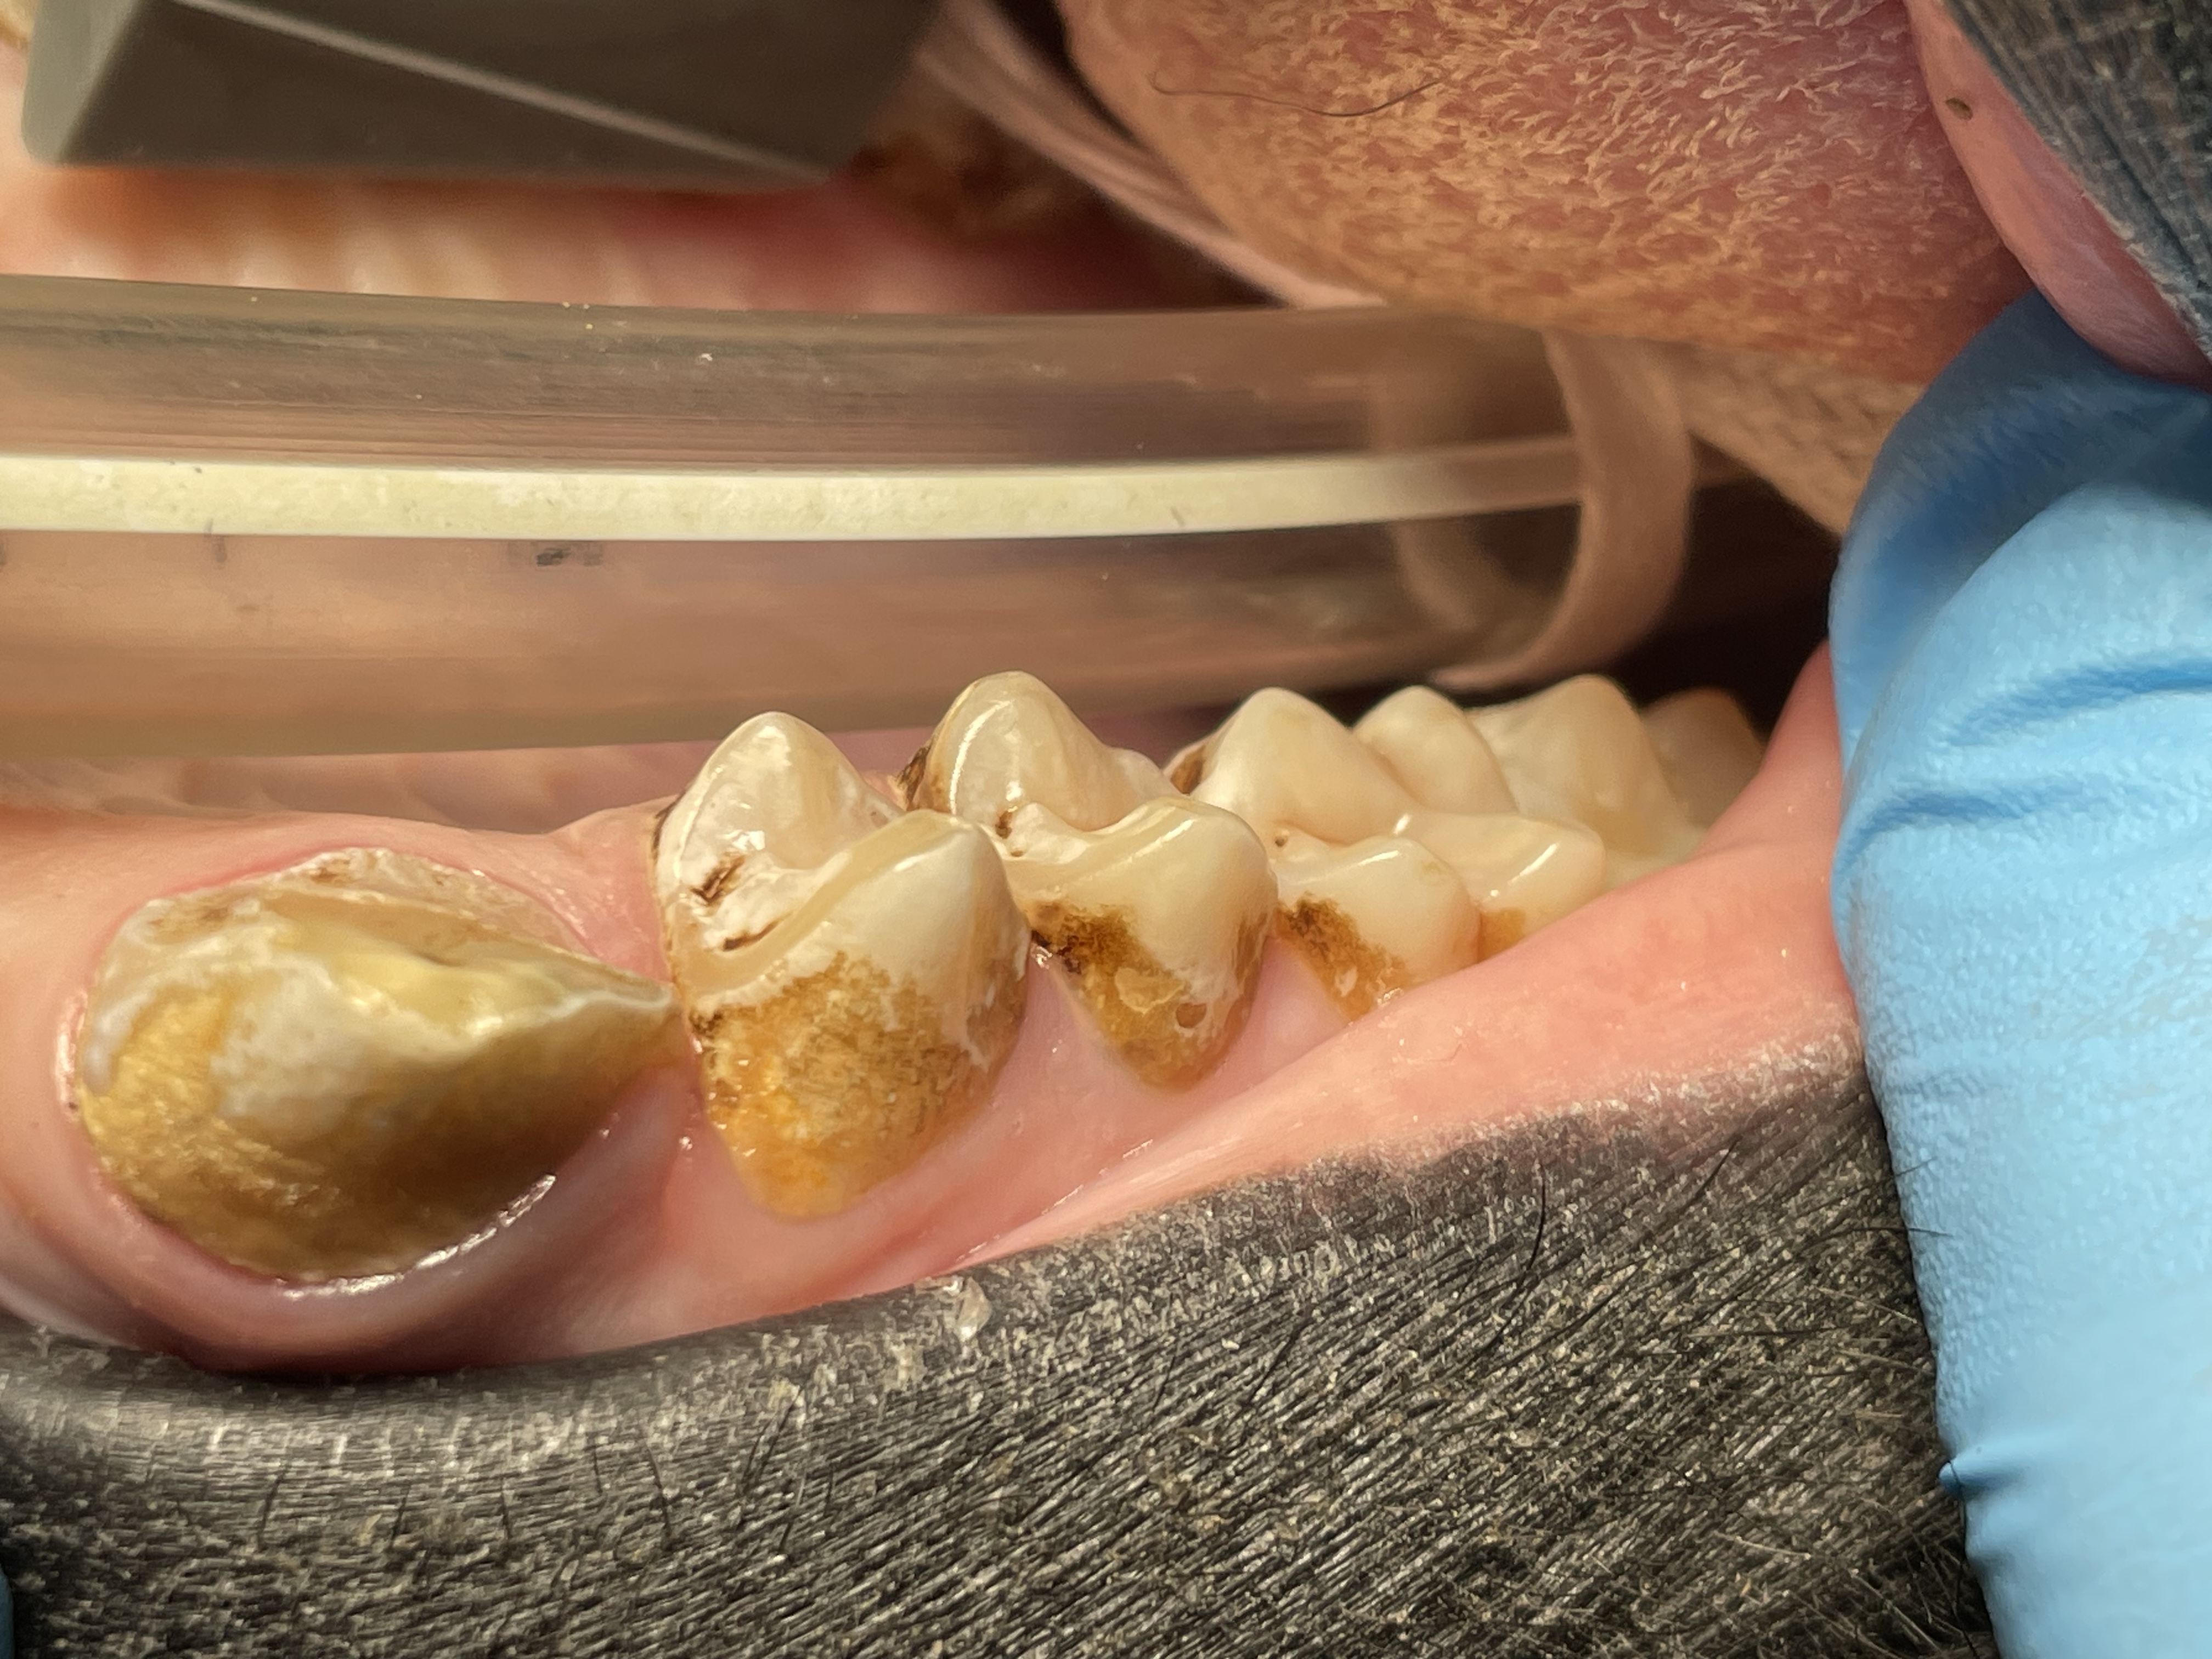

Enamel erosion throughout dentition due to chronic regurgitation/ingestion behavior